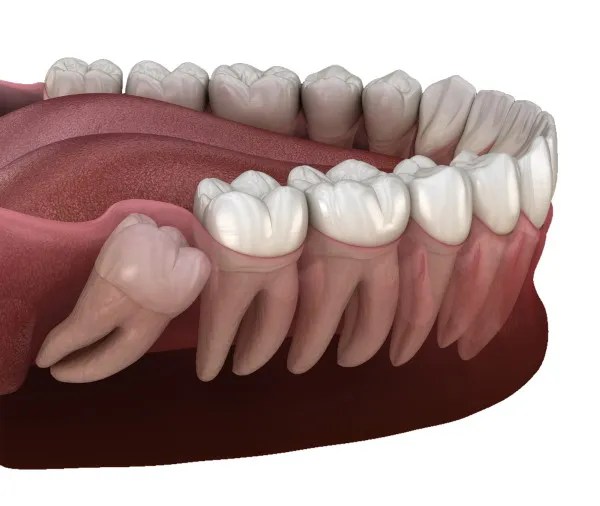

Teeth Removal

- Wisdom Teeth Surgery

- Surgical & Normal Tooth Extractions